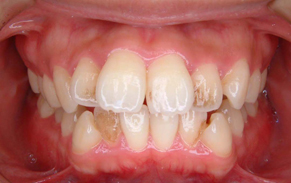

上下前歯のガタガタの症例です。ガタガタしている所は歯ブラシがとどかないので、茶色く着色しています。重なっている所は虫歯になっていることが、ほとんどです。

ガタガタの量が多く、物理的に顎の骨に入りきらないため、上下左右の前から4番目の歯(第一小臼歯)を抜いて、治療しました。抜かずに治療した場合、歯列の円周が広がり口元が突出してしまうため、抜歯をご選択されました。矯正後は歯磨きもし易く、歯の色も一緒にきれいになっています。